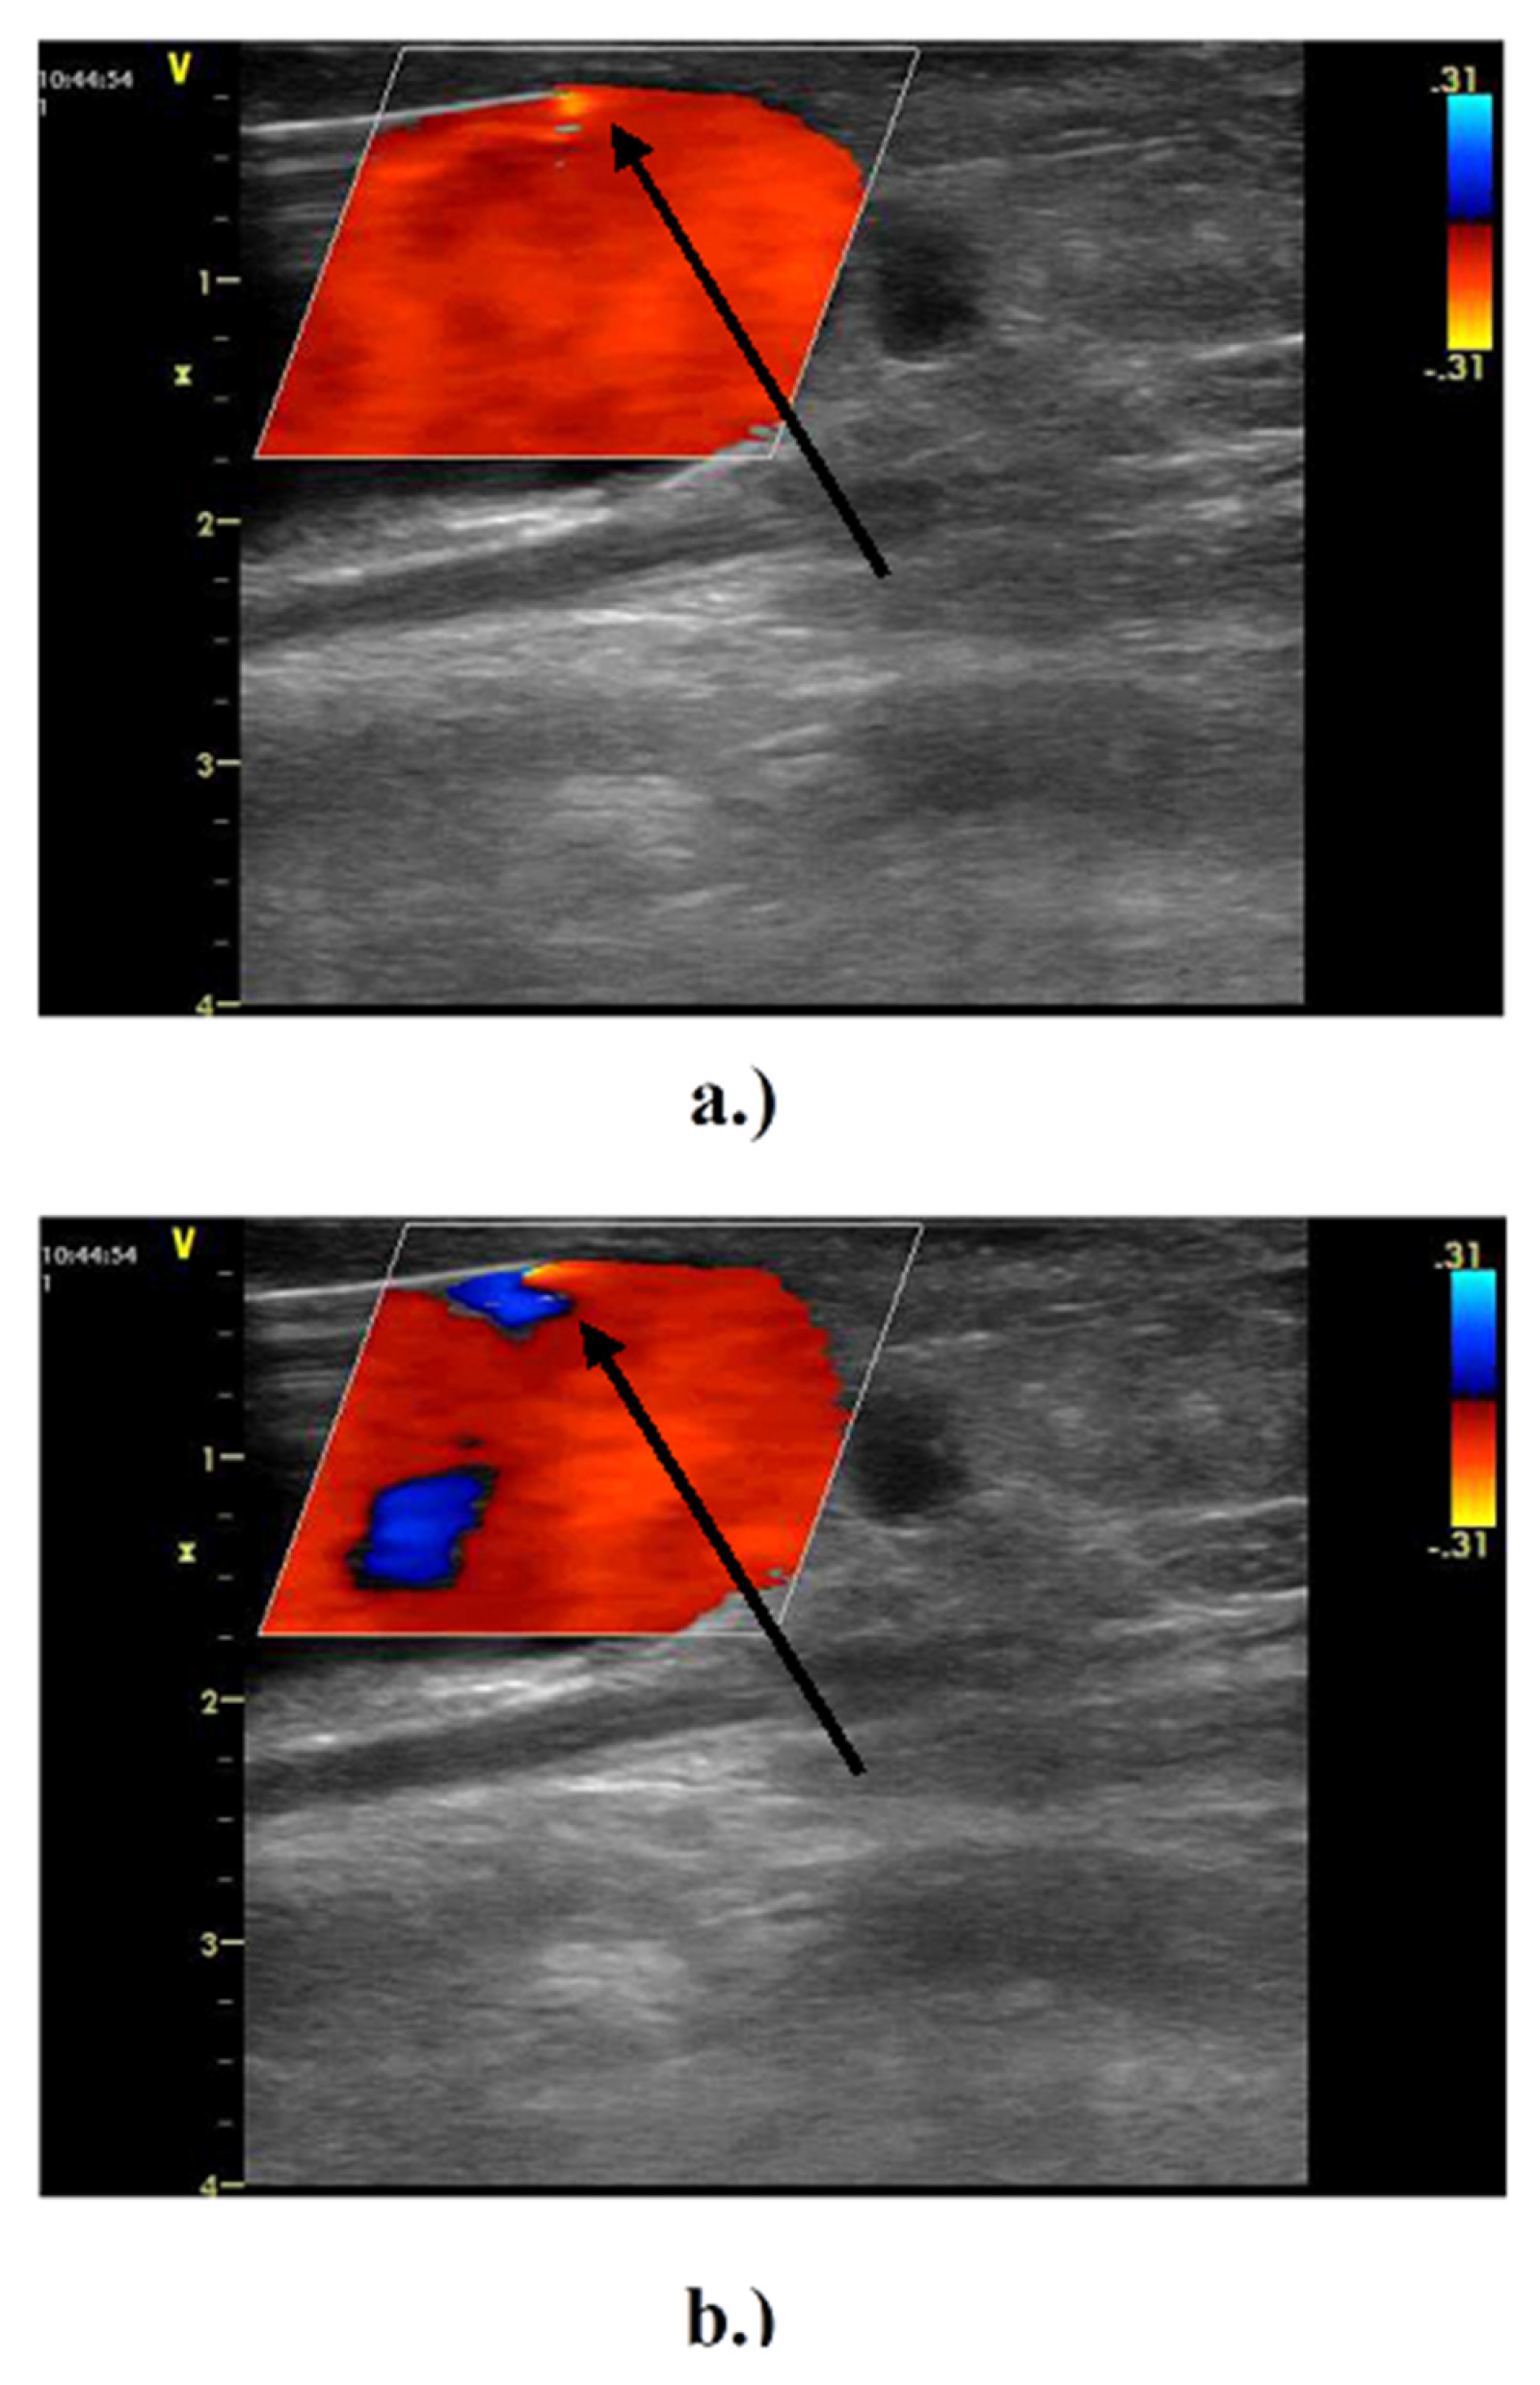

Short-term cyclic flow reversal was evident at the entry into the suctional needle by ultrasonography (Figure 3) in all examined patients.

Figure 3. In vivo measurement of arterial needle blood flow during hemodialysis using Doppler ultrasound. Ipsilateral brachial artery blood flow was 1120 ± 362 mL/min and extracorporeal flow volume was set to 250–300 mL/min. Outflow vein diameter in the area of the punctures was 11 ± 3 mm. The prevailing direction of the flow (suction) at the needle tip (arrow) is highlighted using a lighter red color. (a,b) Flow reversal inside the vascular access at the suction needle due to the peristaltic pump action (small blue area, arrow).